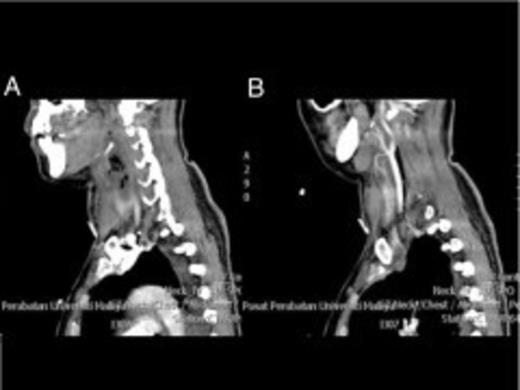

Serial contrast enhanced sagittal images shows a cluster of air within the abscess cavity immediately subhyoid and linear air posterior to the right carotid sheath